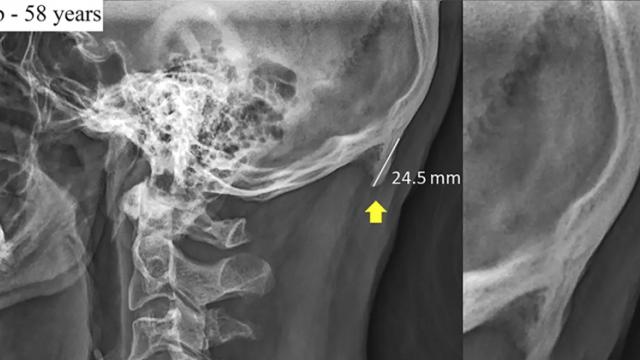

Asa cum arată şi radiografia de mai sus, aşa apar şi "coarnele". Oamenii de ştiinţă sunt îngrijoraţi şi de alte modificări ale muşchilor şi scheletului tinerilor, pe măsură ce utilizarea telefoanelor creşte ca durată. E nevoie de o schimbare de postură, de mod în care stăm pe scaun, în care mergem şi asta trebuie să înceapă de la şcoală.

Studiul pe care îl amintim aici a implicat 1200 de radiografii realizate în Queensland, acoperind un eşantion larg de vârste. O treime dintre aceste radiografii au prezentat excrescenţă osoasă. Frecvenţa a scăzut odată cu creşterea vârstei. În cazurile severe poţi chiar simţi acea parte osoasă în spatele capului, în zona de jos, la atingere.